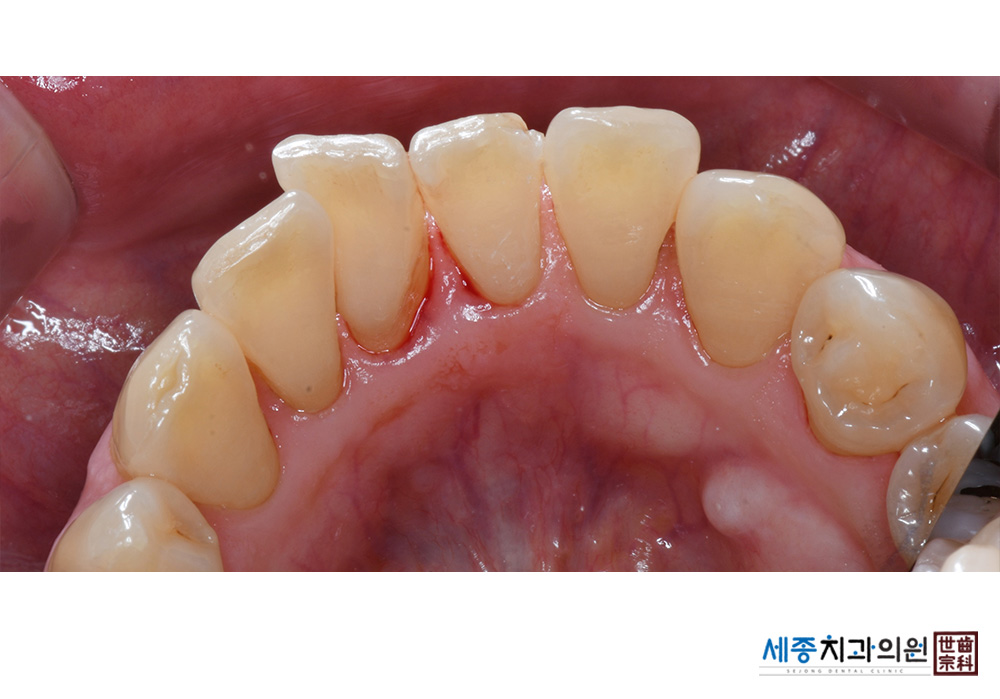

[스케일링] 치주질환 예방 스케일링

치료전 : 2022-05-31

치료후 : 2022-05-31

가글마취&저주파 스켈러를 사용한 스케일링